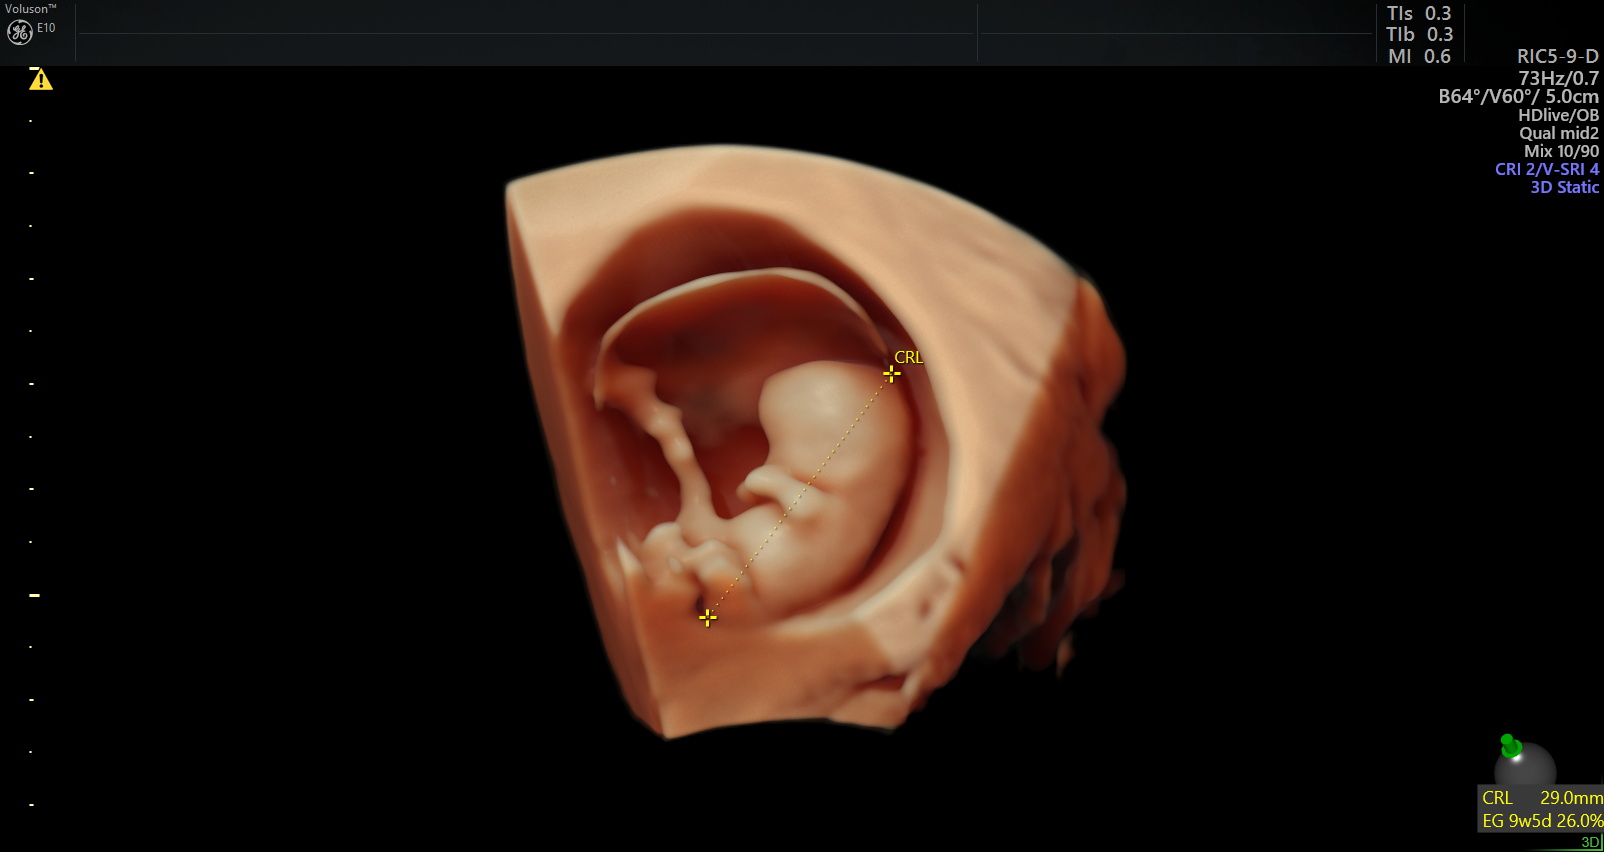

Este es un examen de ultrasonido que se realiza generalmente entre las 4 y 11 semanas de embarazo. Los objetivos de esta exploración son determinar el número de embriones presentes y si el embarazo progresa normalmente dentro del útero.

Esta exploración es útil para las mujeres que experimentan dolor o sangrado en el embarazo y las que han tenido abortos previos o embarazos ectópicos.

INCLUYE:

– Ecografía en HD Live Resolution (5D/7D).

– Estudio Doppler.

– Informe e imágenes impresas en b/n.

– Una foto postal a color.

– Video e Imágenes de la ecografía en MP4 y JPG enviados a su correo electrónico vía nuestra cuenta corporativa en WeTransfer.

– Estacionamiento incluido.

– Explicación de los hallazgos ecográficos.

HASTA LAS 11 SEMANAS.

Este es un examen de ultrasonido que se realiza generalmente entre las 4 y 11 semanas de embarazo. Los objetivos de esta exploración son determinar el número de embriones presentes y si el embarazo progresa normalmente dentro del útero.

Esta exploración es útil para las mujeres que experimentan dolor o sangrado en el embarazo y las que han tenido abortos previos o embarazos ectópicos.

INCLUYE:

– Ecografía en HD Live Resolution (5D/7D).

– Estudio Doppler.

– Informe e imágenes impresas en b/n.

– Una foto postal a color.

– Video e Imágenes de la ecografía en MP4 y JPG enviados a su correo electrónico vía nuestra cuenta corporativa en WeTransfer.

– Estacionamiento incluido.

– Explicación de los hallazgos ecográficos.